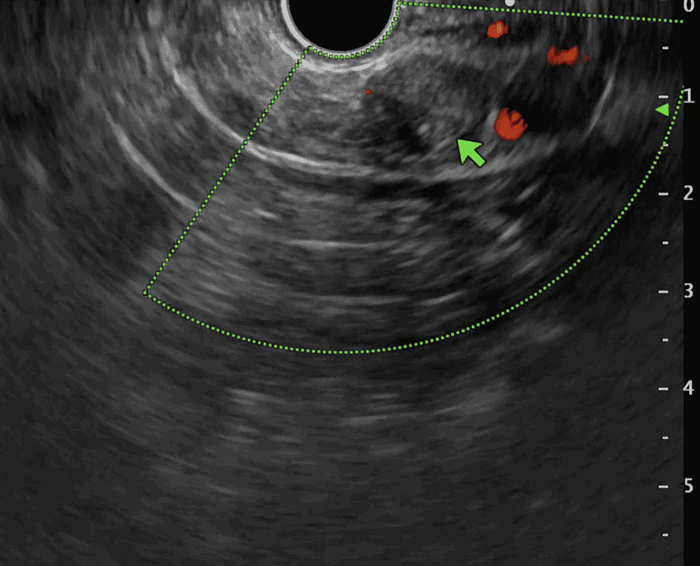

Эндоскопическое УЗИ обладает чувствительностью > 90% в выявлении опухолевого очага. Также может применяться позитронная эмиссионная томография (ПЭТ) КТ не обладает доказанной информативностью; в проведении артериографии или селективной катетеризации воротной и селезеночной вен, как правило, необходимости не возникает.

Эндоскопическое УЗИ обладает чувствительностью > 90% в выявлении опухолевого очага; с этой целью также проводится позитронно-эмиссионная томография (ПЭТ), в то время как КТ не обладает достаточной информативностью.

Выполнение КТ или МРТ с контрастированием помогает выявить инсулиному в поджелудочной железе и точно определить ее местоположение. Однако, в некоторых случаях обнаружение инсулиномы на КТ или МРТ может быть затруднительным. Тогда используется эндоультрасонография или эндоскопическое УЗИ.

Рис.2 Инсулинома на эндоскопическом УЗИ